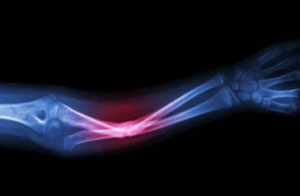

그 밖에도 00골절이라는 말은 많이 있다. 예를 들어 ‘불완전골절’은 흔히 말하는 뼈에 금이 간 상태. 흔히 ‘골절’이라고 불리는 것은 정확하게 ‘완전 골절’이다.

또 ‘복잡골절’로 흔히 착각할 수 있는 뼈가 복잡하게 부러지거나 깨져버린 것을 ‘복합골절’ 혹은 ‘중복골절’이라고 한다. 그 중에서도 뼈가 잘게 부서진 상태의 것은 ‘분쇄골절’이라고 불린다.

이밖에 같은 뼈에 부하가 반복적으로 걸려 피로가 쌓이면서 생기는 ‘피로골절’이나 척추 등에 압력이 가해져 약해진 뼈가 부서진 것처럼 되는 ‘압박골절’이라는 것도 있다.